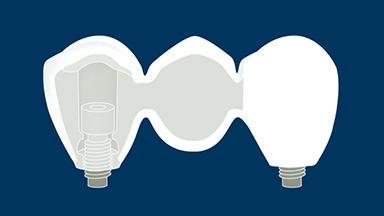

Implant-supported fixed dental prostheses aim to provide replacements for missing teeth that are able to withstand functional demands and accurately mimic the esthetics of the missing dental units.

To achieve this goal, the clinician must select the best available materials to meet the challenges posed by the clinical situation.

This module will discuss the dental materials that are available for the manufacture of implant-supported fixed dental prostheses and the basic principles involved in selecting the material that is best suited for each case.

- describe the ideal properties for dental materials used to fabricate implant-supported fixed dental prostheses (FDPs)

- list the materials that are available to fabricate implant-supported FDPs

- rate available materials against the ideal properties for implant-supported FDP materials